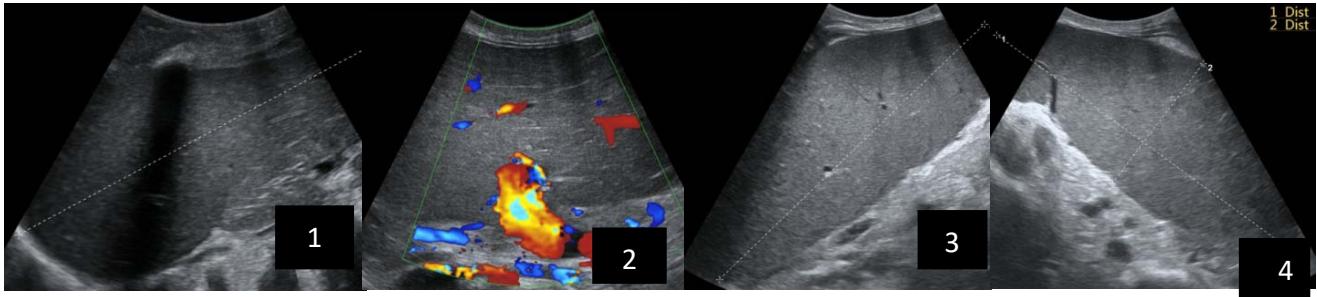

Iconography 1: 54-year-old patient with an intra-splenicsolid mass, anatomopathologically compatible with lymphoma: images 1 and 2: right pleurisy of moderateabundance, image3: celiacadenopathy, image 4: free ascites of moderateabundance, images 5 and 6: intra-splenicsolid mass of around $1418.16\mathrm{ml}$ in B mode and elastographyshowing areas of tumourrigidity, images 7-10: oblique linear images, showingbiopsy gun tracks.

Iconography B: 1 to 4: ultrasound images in mode B showing a large size, 5: ultrasound image in mode B showingsolidhyperechogenic nodules under the capsulorhexis, 6 to 10: ultrasound images in mode B showinglinearhyperechogenic images without overlay in relation to the trajectories of the aiguilles of biopsy.